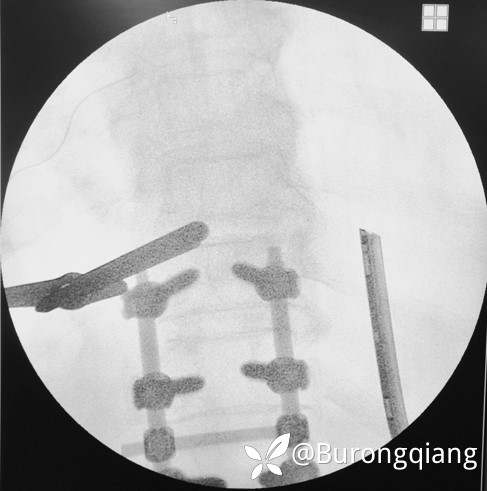

简要病史:患者述2年前无明显诱因出现双下肢大腿憋胀不适症状。外院进一步检查后诊断胸腰椎椎管狭窄,于外院行胸腰椎多节段椎管减压内固定手术治疗,术后症状改善明显,术后10个月再次逐渐出现双下肢麻木无力症状,左侧症状明显,行走时偶有打软腿不适,1年前摔倒致左踝关节骨折,给予内固定手术治疗,术后一直未能下地活动,双下肢麻木无力明显,二便正常。采取保守对症治疗,症状近来逐渐加重。

治疗经过:给予脊柱内镜下椎管扩大减压手术治疗。

术后复查